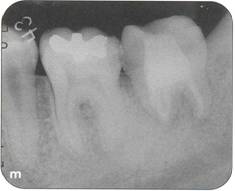

Fi 545e45f g 5-1d Preoperative periapical radiograph. |

|